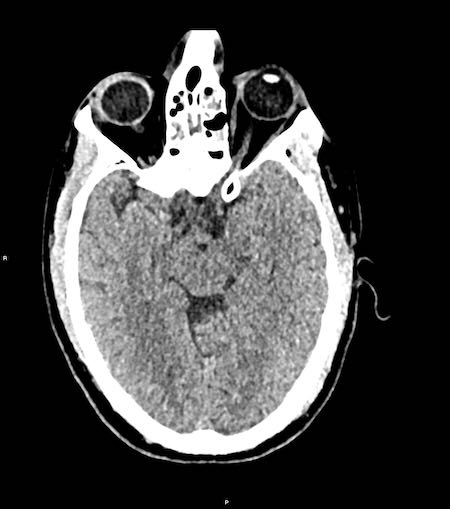

Bệnh nhân này có tụ máu dưới màng cứng cấp tính.

Có sự dịch chuyển đường giữa (hình bên trái).

Bệnh nhân đã được phẫu thuật và khối tụ máu được dẫn lưu (hình bên phải).

Các hình ảnh cho thấy tụ máu dưới màng cứng.

Lưu ý rằng khối tụ máu có cả vùng tăng tỷ trọng và đồng tỷ trọng.

Hình ảnh này có thể gặp trong chảy máu siêu cấp tính, nhưng cũng có thể gặp trong trường hợp chảy máu tái phát.

Có sự dịch chuyển các cấu trúc đường giữa kèm tắc nghẽn lưu thông dịch não tủy, dẫn đến giãn sừng thái dương của não thất bên phải (mũi tên).